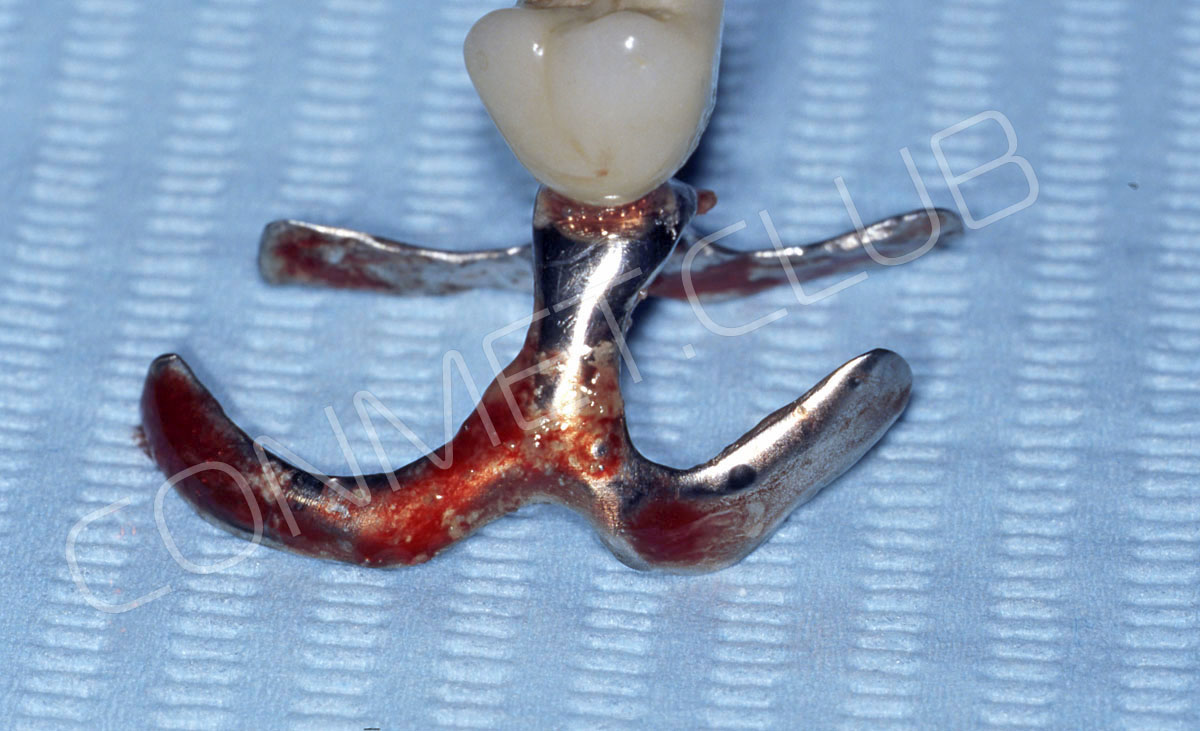

Имплантат напечатали из особого, биосовместимого, медицинского титана на предприятии имеющим соответствующую медицинскую лицензию. Толщина имплантата составила 0,8 мм, а вес всего несколько грамм!

Сама же операция длиться 20-50 минут в зависимости от количества утраченных зубов. В процессе этой операции, после проведенной местной анестезии, делается разрез на слизистой, она приподнимается и субпериостальный имплантат укладывается на кость. После этого рана фиксируется несколькими швами и все! Через 10-14 дней мягкие ткани срастаются и надкостница надежно удерживает имплантат на месте. Нет необходимости ждать несколько месяцев, как это бывает в случае с внутрикостными винтовыми имплантатами.